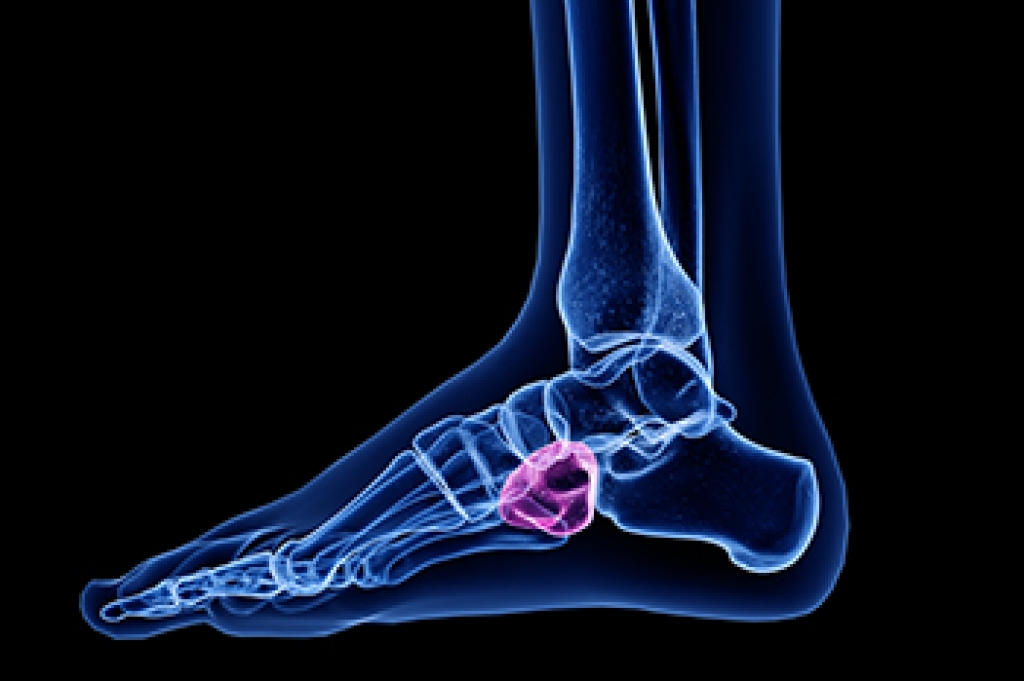

Cuboid syndrome is a condition where the cuboid bone, located on the outer side of the foot, becomes misaligned, causing pain and difficulty in movement. This syndrome often results from repetitive stress or trauma, leading to discomfort and instability in the foot. The cuboid whip is a manual therapy technique used to address this issue. During the procedure, a podiatrist applies a specific, quick, and controlled thrust to the cuboid bone, aiming to realign it and restore proper foot function. This adjustment can help to alleviate pain, improve mobility, and address any associated discomfort. If you have pain in this part of your foot, it is suggested that you contact a podiatrist who can accurately diagnose if it is cuboid syndrome, and treat it accordingly.

Cuboid syndrome is a common cause of lateral foot pain, which is pain on the outside of the foot. The condition may happen suddenly due to an ankle sprain, or it may develop slowly overtime from repetitive tension through the bone and surrounding structures.

Diagnosis of cuboid syndrome is often difficult, and it is often misdiagnosed. X-rays, MRIs and CT scans often fail to properly show the cuboid subluxation. Although there isn’t a specific test used to diagnose cuboid syndrome, your podiatrist will usually check if pain is felt while pressing firmly on the cuboid bone of your foot.